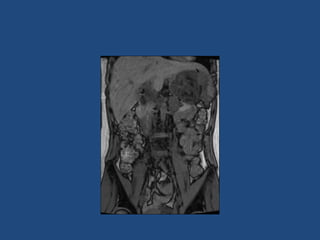

Adrenal imaging

Imaging

•

>6cm high suspicion of malignancy

3-6cm repeat imaging in 3-6M

Delayed washout on contrast is suggestive

most are often inhomogeneous, irregular

margins

• Look for invasion of IVC

• Always do CAP and consider bone scan and

pet if in doubt

• Don’t ever biopsy (tumour spill)

Imaging • • • • >6cm high suspicionof malignancy 3-6cm repeat imaging in 3-6M Delayed washout on contrast is suggestive most are often inhomogeneous, irregular margins • Look for invasion of IVC • Always do CAP and consider bone scan and pet if in doubt • Don’t ever biopsy (tumour spill)